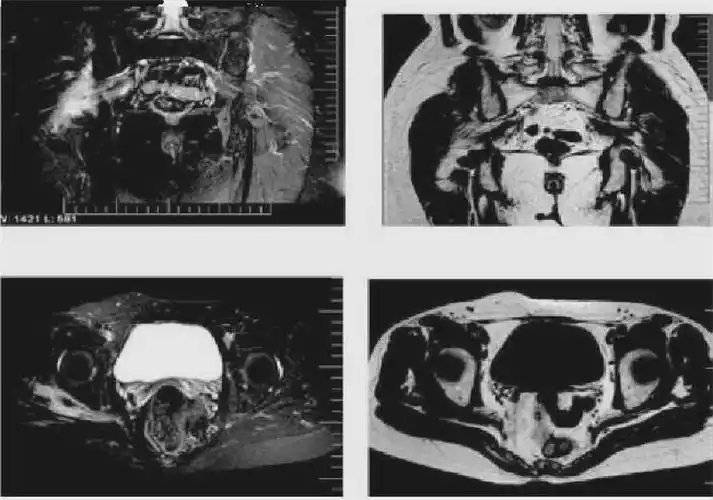

梨状肌综合征的解剖评估诊断及康复治疗

术前mri

骨盆肌肉mri断层解剖